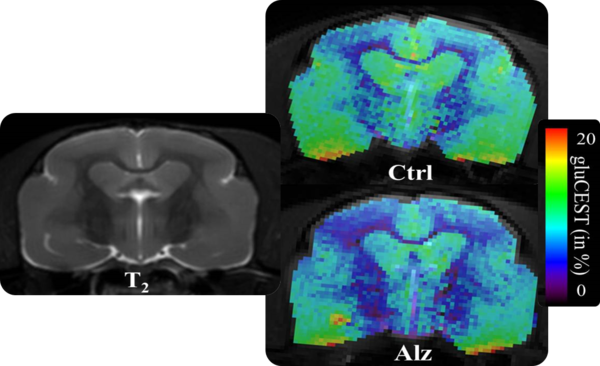

• Complete RF coil portfolio for mice and rats available, including coils for head, brain, cardiac, spine, body, multi-channel array coils with up to 8 channels, and x-nuclei

• Over 100 validated and ready to use in vivo protocols and scan programs for mice and rats

• MRI sequence portfolio of more than 1,000 sequence variations, including wireless cardiac imaging using navigator based IntraGate methods with cartesian or radial readout, as well as short echo time imaging, such as UTE and ZTE